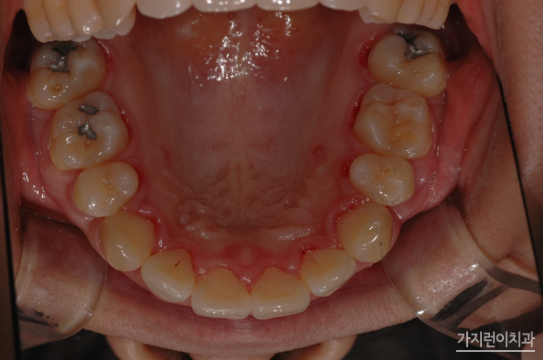

최근 인터넷을 통해 의학 정보 공유를 하는 분들이 늘고 있는데요. 비의료인들이 자신들의 구강사진을 올리며 서로 진단을 내려주는 경우가 있습니다. 또 비급여 수가를 비교해 이를 그대로 치과의사에게 들이미는 경우도 있다고 하는데요. 충치치료는 치과의 근본이라고 할 수 있습니다. 기본이 되는 치료라는 건데요. 치아교정과 같은 큰 치료를 앞두고 있다면 사전에구강에 문제가 없는지 충치나 잇몸은 괜찮은지를 점검 후 문제가 있다고 판단이 된다면 바로 치료를 하는 것이 좋습니다.

- 충치치료 및 잇몸치료